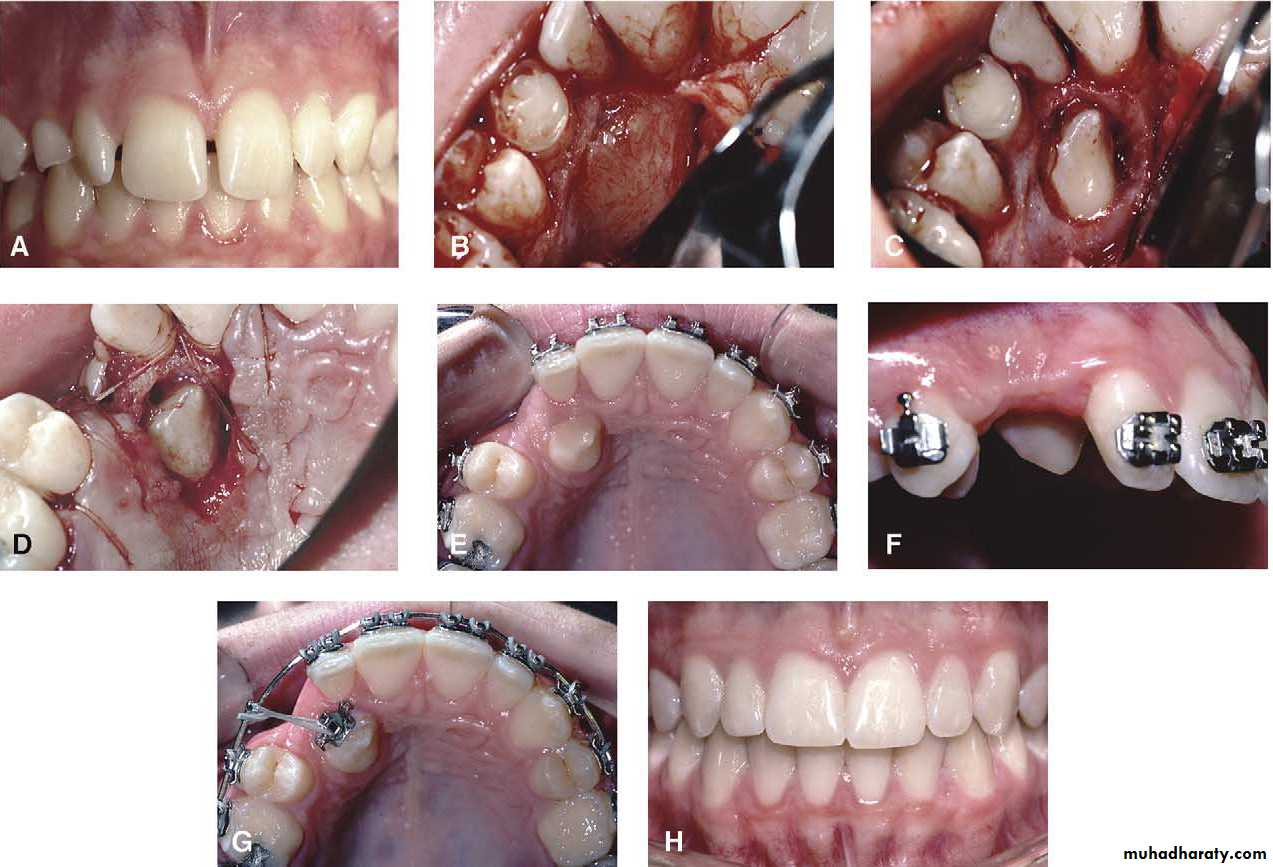

Extraction by the palatal approach

The length of the palatal incision will depend upon whether one or two impacted canines are to be removed .if two canines required extraction the incision line runs in the gingival crevice from the first molar region in one side to the first molar in the opposite side . But if only a single canines to be removed the incision extend from the first molar in the side of operation to the canine of the other side .Mosul university- College of dentistry-oral & maxillofacial surgery department

The mucoperiosteal flap is raised with a Howarth periosteal elevator ,working from each side toward the midline .the neurovascular bundle passing through the incisive foramen should be divided with a sharp scalpel close to the bone .

Mosul university- College of dentistry-oral & maxillofacial surgery department

Once the palatal mucoperiosteal flap has been raised , the crown of the tooth may be immediately visible , or a bulge may present in the palate and there is a thin layer of bone overlying the crown . The bone should be removed to expose the neck of the impacted tooth .

If the impacted canine is lying in close proximity to adjacent teeth , bone removal must be restricted to the palatal and distal aspect of the tooth .this approach will reduce the risk of damage to the root of adjacent incisor or premolars . After exposing the crown of the tooth , it can be extracted with Copland chisel elevator , otherwise tooth sectioning is required .

When the root of the canine lies across the alveolar process between the root of the standing teeth , in this case both palatal and buccal flaps are raised .

A thin acrylic palatal splint held in place by a clasp on the first molars , will prevent the formation of a hematoma beneath the palatal flap .